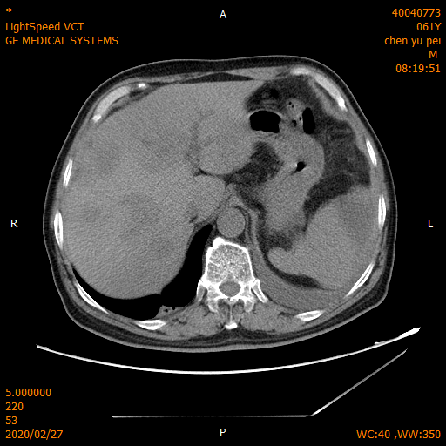

2020-02-04 CT

肝脏多发异常强化灶,考虑转移。

横结肠-降结肠交界处壁增厚强化,请结合消化道检查,腹腔部分肠管扩张积气积液,可见气液平,请结合临床。

2020-02-27 增强CT报告:

肝脏多个略低密度影,考虑转移灶,结合临床;脾脏外缘积液;

胆囊略大;前列腺钙化灶;腹腔积液;左中下腹术后改变;

腹盆腔、后腹膜多发淋巴结,局部肿大;双侧腹股沟小淋巴结。